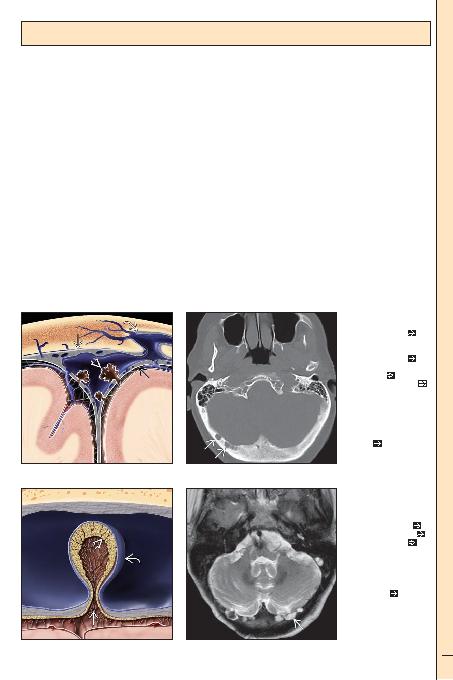

apekste superior sagital sinüs

(SSS) ve venöz gölcük

yaprak tarafindan oluturulur:

di (periosteal) yaprak

granülasyonlar

yapiiktir. (Sa) Aksiyel kemik

BT'de, araknoid granülasyon

için tipik olan transvers sinüse

komu, keskin sinirli, lüsent,

çok sayida oksipital kemik

lezyonlari

SSS'ye projekte olan araknoid

granülasyonun koronal çizimi.

Araknoid granülasyon içine

uzanan BOS çekirdeini

BOS'un venöz dolaima drena-

jini salarlar. (Sa) Aksiyel T2A

YB MR'de oksipital kemikte,

tipik lokalizasyonda, araknoid

granülasyonlara

mektedir